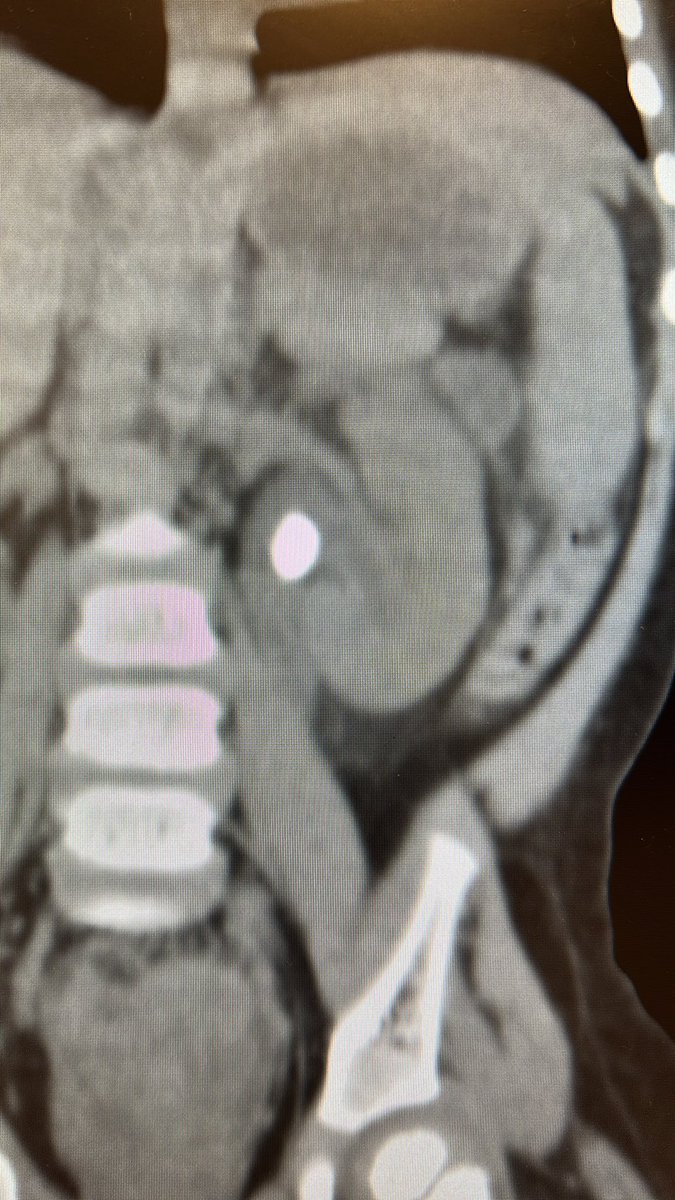

Propondrías una litotricia extracorpórea a paciente menor de 2 años, con antecedente de Pielonefritis aguda y litiasis renal de 12 mm? Cuánto tiempo después? / Would recommend SWL to under 2 yo after acute pyelonephritis? Time? #lupeyenchile #pedsendourology #endourologiaped